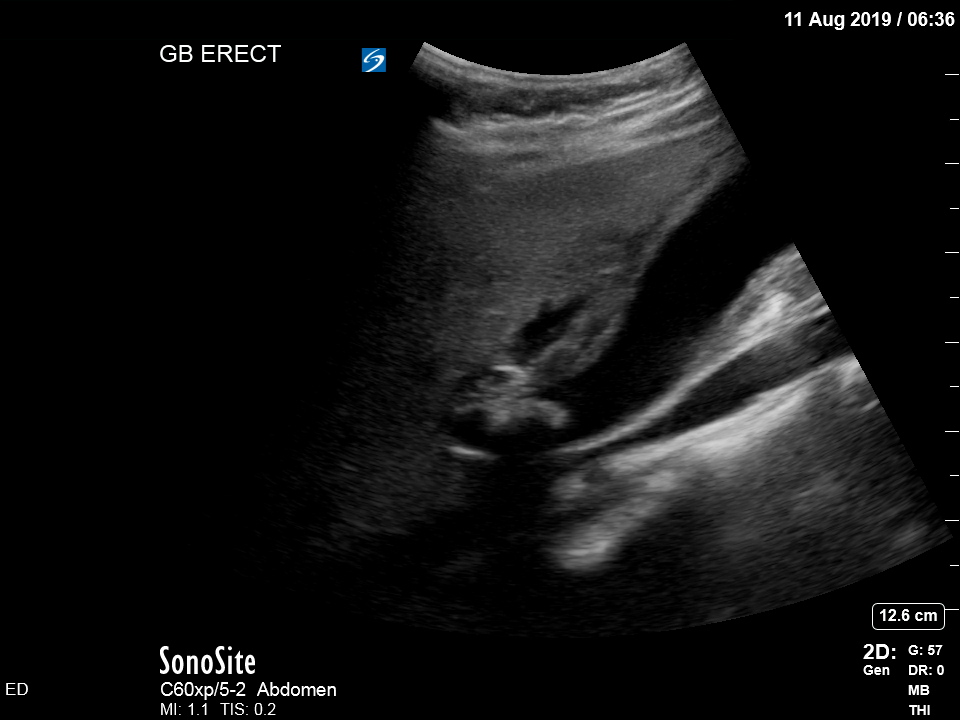

The treating house officer suspected an alternative pathology and bedside ultrasound was performed.

The appearance is typical of acute cholecystitis. The patient was started on IV antibiotics. Images were shown to the surgical registrar who accepted the patient for admission. Formal ultrasound confirmed the findings and the patient went for laparoscopic cholecystectomy within 24hrs. At operation, there was a grossly inflamed gallbladder with an 11mm stone in the neck.

Ultrasound is the formal imaging study of choice for diagnosing gallstones and acute cholecystitis, which makes it a particularly useful POCUS study. The four sonographic signs of acute cholecystitis are:

- Cholelithiasis (stones in the gallbladder, especially if non-mobile)

- Gallbadder wall thickening (there are various published criteria and rules of thumb but generally >4mm is considered abnormal – though it is more about the edematous/irregular appearance than the specific number)

- Pericholecystic fluid

- Sonographic Murphy sign (the patient is tender when the probe presses on the gallbladder)

Notice the typical appearance of the gallstone – the anterior face reflects ultrasound producing a hyperechoic (bright) surface. Because no sounds waves pass through the stone, the area behind it cannot be imaged and instead we see the artefact known as posterior acoustic shadow.